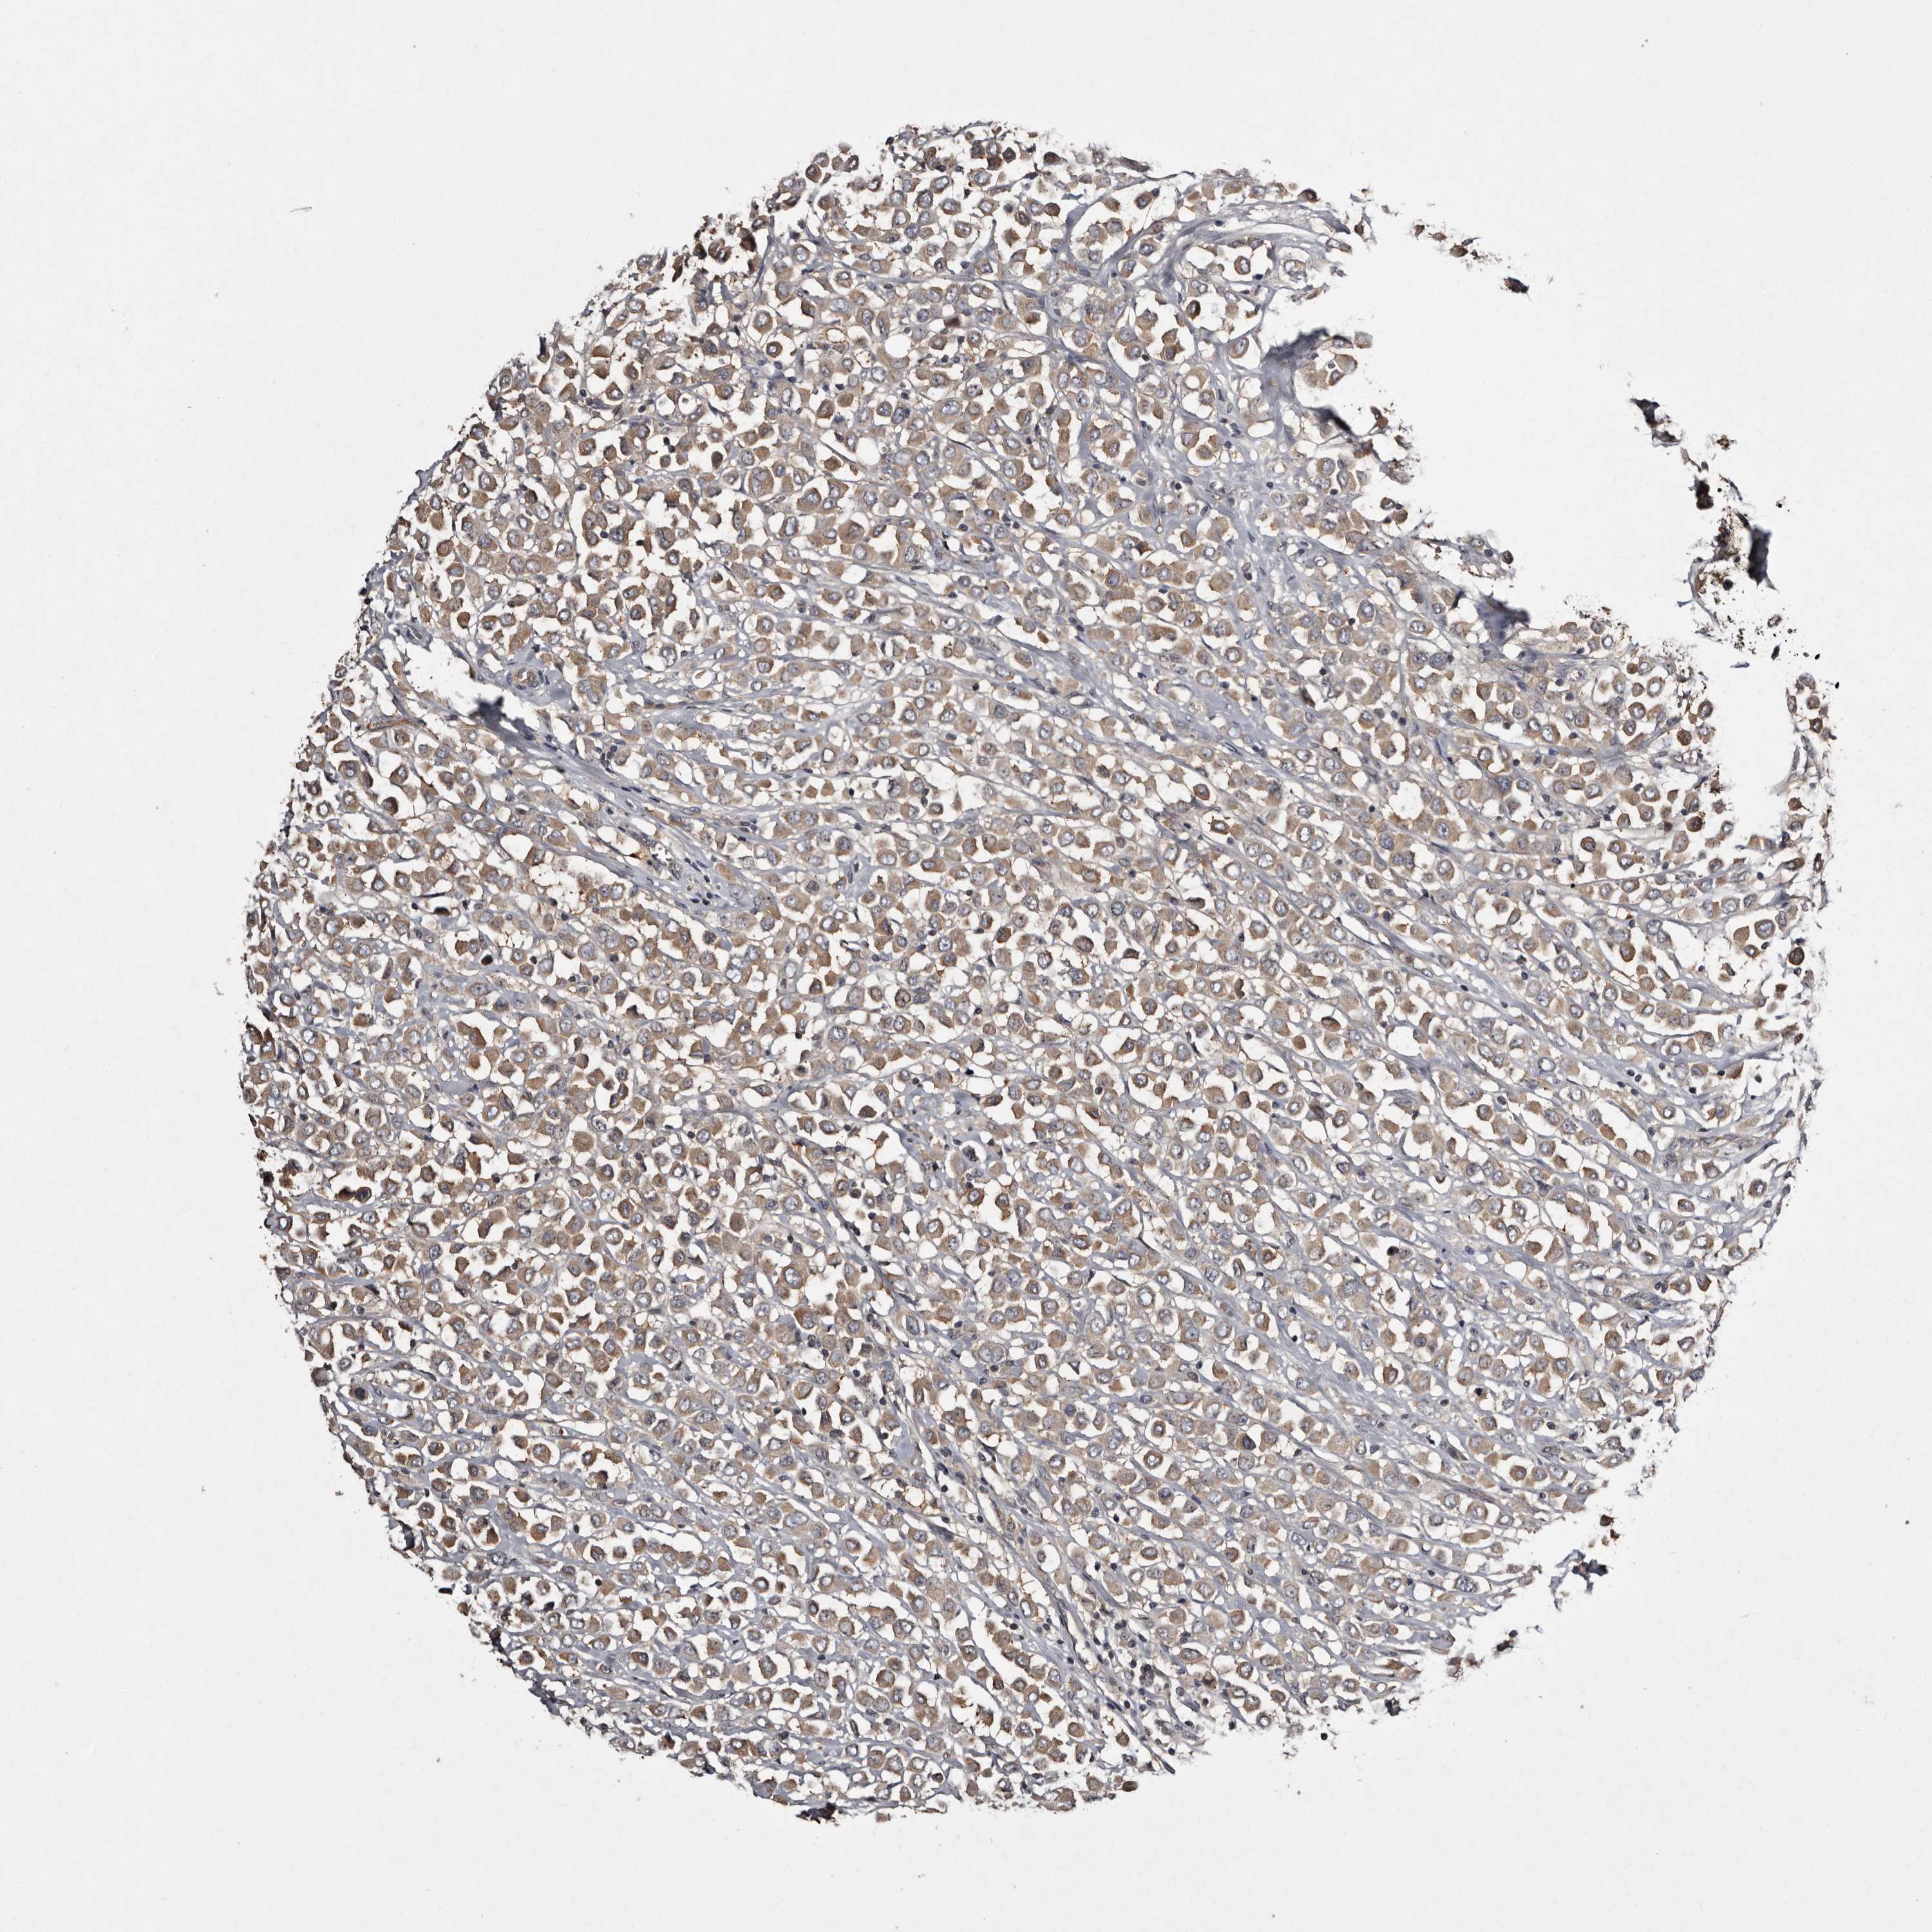

CANCER BREAST CANCER Show tissue menu

BRCA TCGA BRCA VALIDATION PROTEIN EXPRESSION